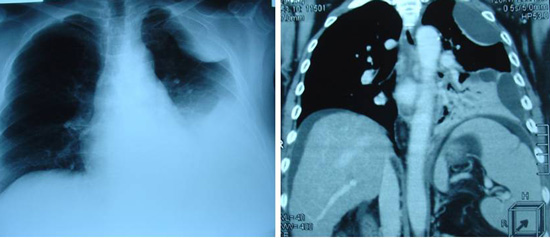

Tidak puas, PC lalu pergi ke sebuah rumah sakit swasta di Ipoh. Pada pemeriksaan X – ray didada kirinya menunjukkan adanya efusi pleura (yaitu adanya cairan di paru-paru kirinya). Cairannya disedot keluar. Sebuah ultrasonagraphy ( dibagian perut ) pada tanggal 23 September 2009 menunjukkan sebuah lesi berukuran 2,6 cm ( diperkirakan hepatoma atau kanker hati) di lobus sebelah kanan. Selain itu, pada organ hatinya sudah terjadi sirosis hati ( mengeras ) dengan hipertensi portal dan adanya ascites ( adanya cairan dibagian perut ). Organ Limpa nya membesar.

Biopsi dari lesi tersebut tidak dapat dilakukan mengingat telah terjadinya ascites, trombosit yang rendah dan keberadaan tumor yang terlalu dalam dan berdekatan dengan vena portal.